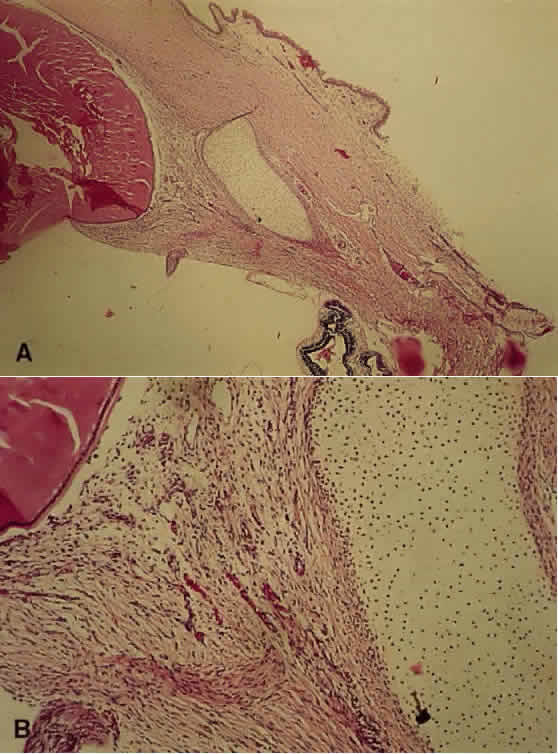

2. Microphthalmia with cyst is the extreme example of a colobomatous defect and is caused by a complete failure of the fetal fissure to close. The fetal fissure, located inferonasally, exists transiently for the entrance of embryonic vessels, and its closure normally occurs at the 15-mm stage. The resultant cyst may be larger than the microphthalmic eye and is generally lined with neuroectodermal tissue (Fig. 1).12

Fig. 1. Microphthalmia with cyst. A. The microphthalmic left eye in a 2-year-old girl. B. Computed tomographic scan showing the cyst nasal to the microphthalmic eye. C. Gross specimen, showing that the cyst is larger than the eye. D. Low-power photomicrograph showing the relatively well-formed eye and large cyst (H&E, × 1). There is focal retinal dysplasia. (UTHSC-SA EP 169. Courtesy of Charles R. Leone, MD)